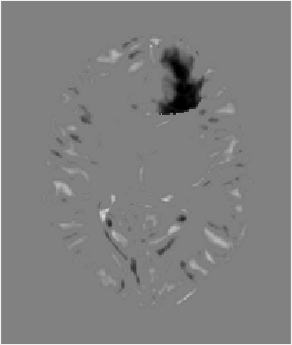

Fig. 3: Example atlas-to-image registration errors [mm]: (a) tumor; (b) LRS; (c) PCA model w/o regularization; (d) PCA model w/ one step of regularization; (e) PCA model w/ two steps of regularization.

Fig. 2 shows atlas-to-image registration results for images with and without tumor, LRS reconstruction and our PCA-based models with and without regularization. Fig. 3 shows the spatial error distributions, compared to the ground truth registration. We use NiftyReg [17] (with standard settings) and NCC for registrations. Errors are computed using Euclidean distance. Direct registration of the tumor image results in large registration errors. Registration to the low-rank reconstruction greatly reduces the error in the tumor areas but retains errors near the cortex, mainly due to its blurry reconstruction. Our PCA models further reduce registration errors in the tumor areas and keep errors near the cortex low.